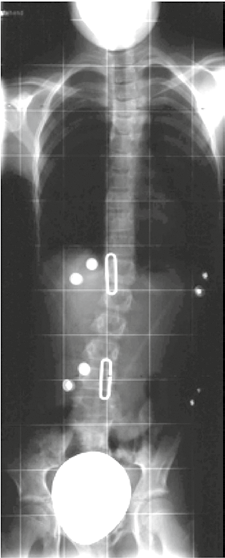

Alle erfolgreichen modernen Weiterentwicklungen der Derotationsorthesen wie z. B. die Korsette nach Rigo System Chêneau (RSC) oder Chêneau light streben eine Spiegelung des Krümmungsmusters und eine Überkorrektur an. Wenn diese Spiegelung nicht erreicht wird, kommt es zu keiner suffizienten Besserung der Skoliose (Abb. 2). Durch Spiegelungskorsette kommt es nicht zur exakten Spiegelung des Cobb-Winkels, sondern nur zu einer Verringerung desselben (Abb. 3). Wichtig erscheint aber nicht nur die Spiegelung, sondern auch die Schaffung ausreichender Freiräume, in die hinein geatmet werden kann und die somit für eine aktive Korrektur sorgen. Insbesondere dorsal ist ein entsprechender Raum wichtig (Abb. 4).

Für die meist jungen Patientinnen steht nicht der gemessene Cobb-Winkel im Vordergrund. Zwar ist dies ein Parameter, an dem sich der Therapieerfolg messen lässt, dennoch erscheinen Symmetrie und kosmetische Aspekte für die Patientinnen wesentlich wichtiger. Das behandelnde Team, bestehend aus Orthopäden, Orthopädie-Technikern und Physiotherapeuten, muss sich also auch hieran messen lassen. Ein kosmetisch gutes Ergebnis (siehe Abb. 3a, b u. 5a, b) entschädigt für eine jahrelange Versorgung mit einem Korsett, die zu einer deutlichen Minderung der Lebensqualität führt 10. Gut derotierende Rumpf-Korsette haben auf eine mehr oder minder weiche Wirbelsäulen-Verkrümmung der noch wachsenden Jugendlichen einen passiven oder aktiven Korrektur-Effekt. Es stellt sich jedoch die Frage, ob neben der meist guten passiven Korrektur in einem modernen derotierenden Rumpf-Korsett auch eine entsprechende aktive Aufrichtung durch die Jugendlichen möglich ist.